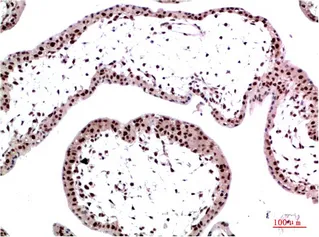

HP-1γ(3B9)Mouse Monoclonal Antibody

Cat: AMM12189

Size1:50μl Price1:$118

Size2:100μl Price2:$220

Size3:500μl Price3:$980

Size2:100μl Price2:$220

Size3:500μl Price3:$980